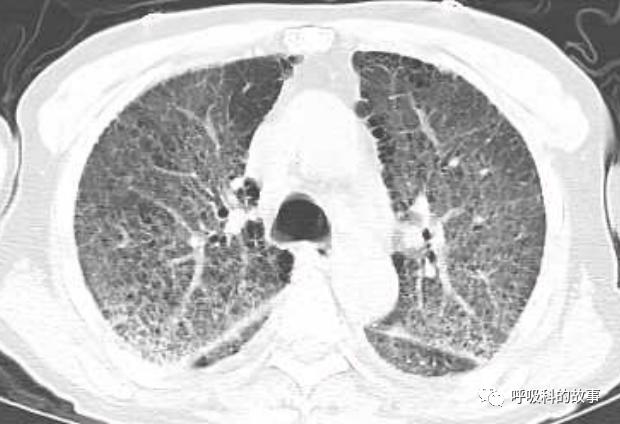

上周,我去会诊一个病人又出现了类似的情况,一个72岁的男性病人因为发生十二指肠球部溃疡穿孔入住我院胃肠外科,给予腹腔镜下十二指肠球部溃疡穿孔修补术。术后由于患者禁食就给予了大量的补液,大约有3000多毫升,其中0.9%氯化钠盐水(也就是我们通常所说的生理盐水)一共是补了接近2000ml,同时还补了1500ml的营养液呢。患者术后第二天晚上开始出现呼吸困难,程度进行性加重,到了术后的第五天,呼吸困难非常明显了,病人也出现端坐位呼吸,两肺出现严重的肺水肿转入ICU治疗。